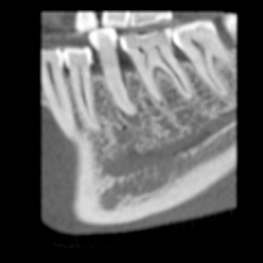

Höga upplösningar och standarddoser är inte alltid nödvändigt – ofta räcker det med lägre dos och upplösning. Planmeca Ultra Low Dose är tillräcklig för att se den mandibulära nervkanalen för implantatplanering och extraktion av visdomstand, till exempel. Allt kan göras med en otroligt låg dos.